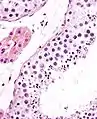

Seminiferous tubule in cross-section (large tubular structure – center of image) with sperm (black, tiny, ovoid bodies furthest from the outer edge of the tubular structure). H&E stain.

The epithelium of the tubule consists of a type of sustentacular cells known as Sertoli cells, which are tall, columnar type cells that line the tubule.

In between the Sertoli cells are spermatogenic cells, which differentiate through meiosis to sperm cells. Sertoli cells function to nourish the developing sperm cells. They secrete androgen-binding protein, a binding protein which increases the concentration of testosterone.